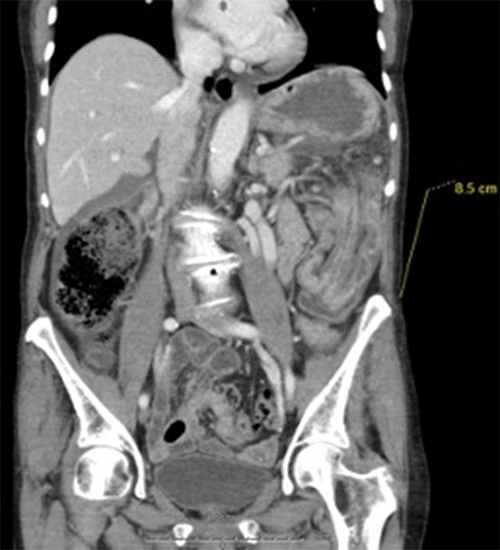

Proximal to the lesion, there was significant colonic dilation, with the cecum measuring approximately 9.5 cm in diameter (Figure 2). Fat stranding in the left mid abdomen and a moderate amount of ascites in the abdomen and pelvis was also identified. Laboratory values were significant for white blood cell (WBC) count of 12.8 × 103.0 cells/uL (reference range 3.7-10.68 × 103.0 cells/uL) with a shift of 84.6% (normal limit 40-70%) and lactic acid of 0.8 mmol/L (normal limit 0.5 to 2.2 mmol/L) as well as CEA 2.0 ng/mL (normal limit 0-2.5 ng/mL).

Figure 2. CT Abdomen Showing Colonic Dilation with Cecum Measuring Approximately 9.5 cm in Diameter. Published with Permission